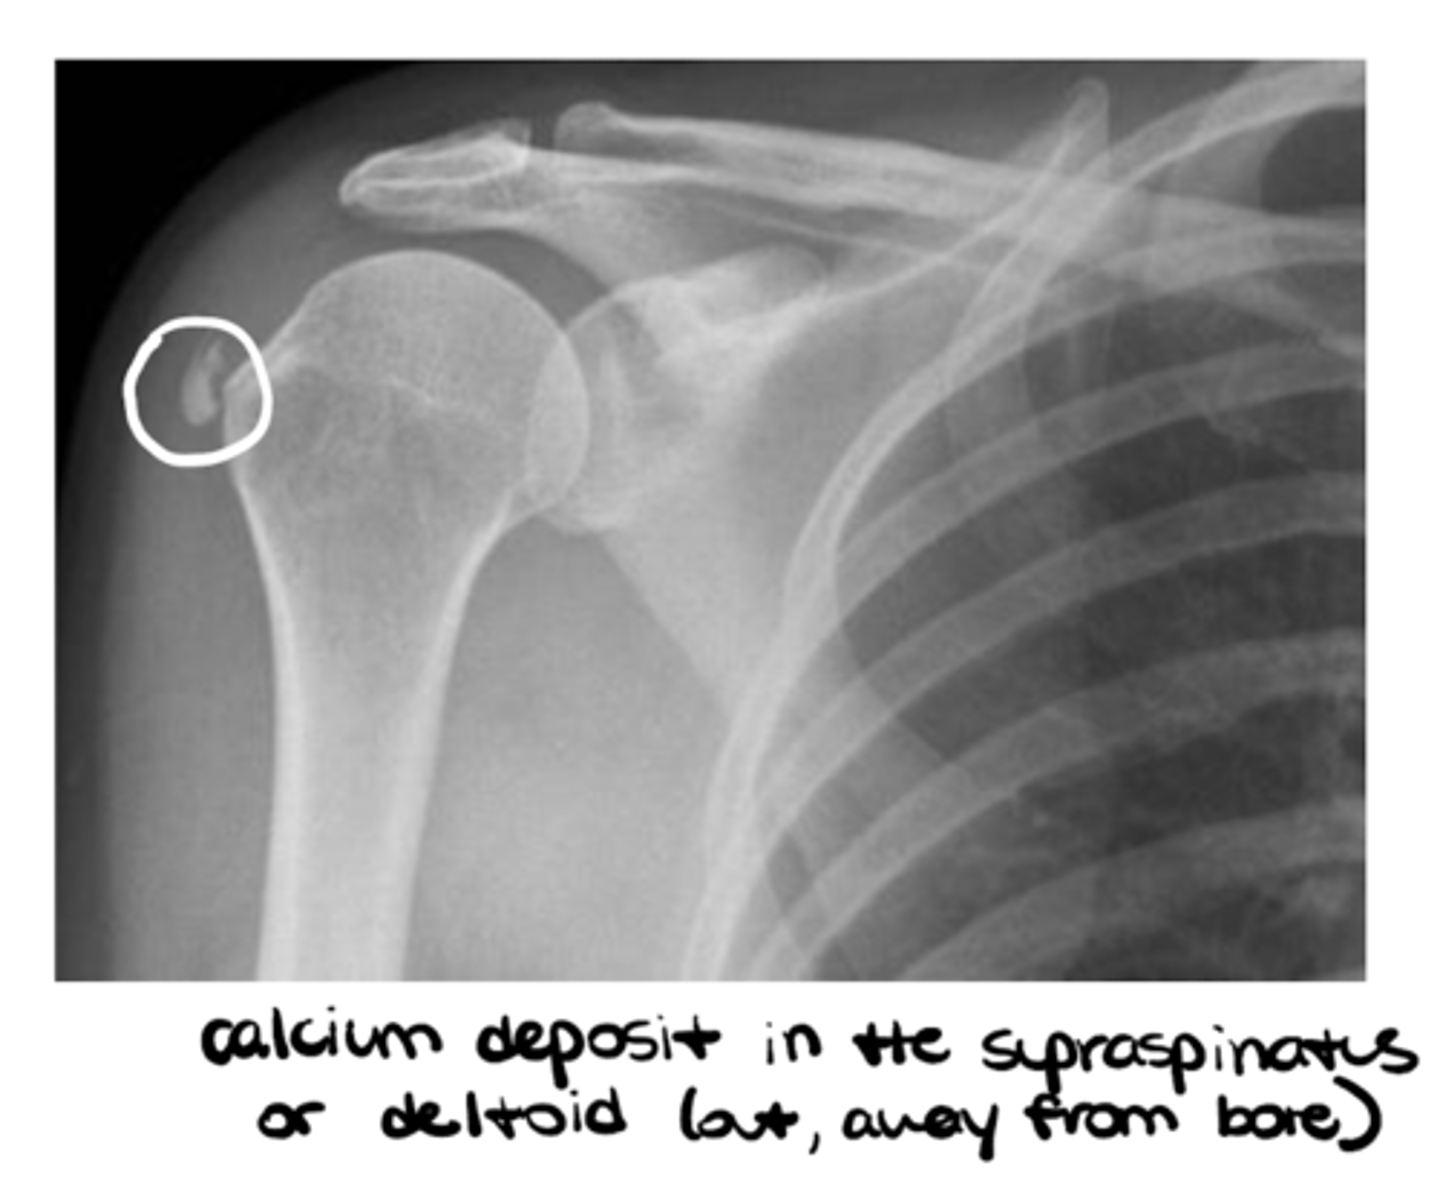

List the sub-components of (S) soft tissues: miscellaneous

- Foreign body

- Calcifications